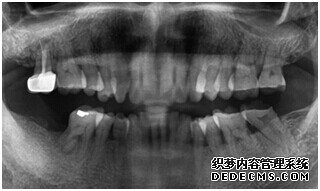

刘女士牙齿拍片初步检查

由CT片检查来看,刘女士口腔健康环境还是很好的,牙槽骨也适合种植牙的条件,而且由我们最后一颗牙是非常重要的,经过专家的建议和详细解释了原因之后,刘女士选择了美国百康种植牙。